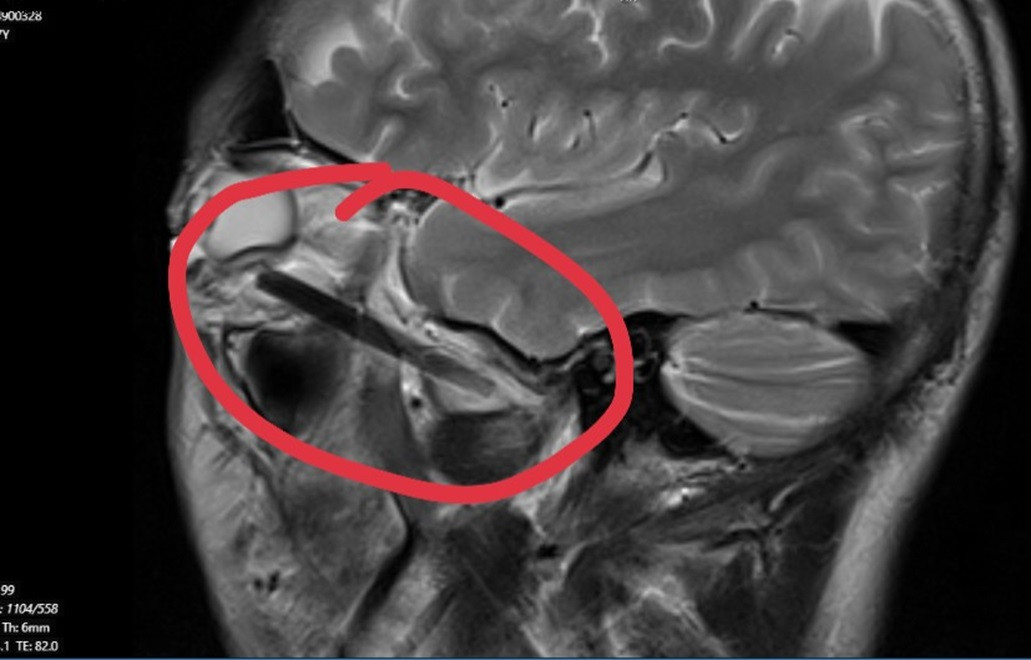

Trước đó, anh T.N.B (ngụ Bình Dương) có triệu chứng nhức mắt nên đến Bệnh viện Đa khoa tỉnh Bình Dương để khám. Sau khi tiến hành chụp MRI, các bác sĩ phát hiện bên trong hốc mắt của anh B. có dị vật dài khoảng 6cm giống như chiếc đũa.

Sau hội chẩn, các bác sĩ phẫu thuật lấy ra dị vật là một đoạn đũa gỗ dài 6cm. Hiện tại, bệnh nhân đã ổn định và đang được theo dõi sức khỏe tại bệnh viện.